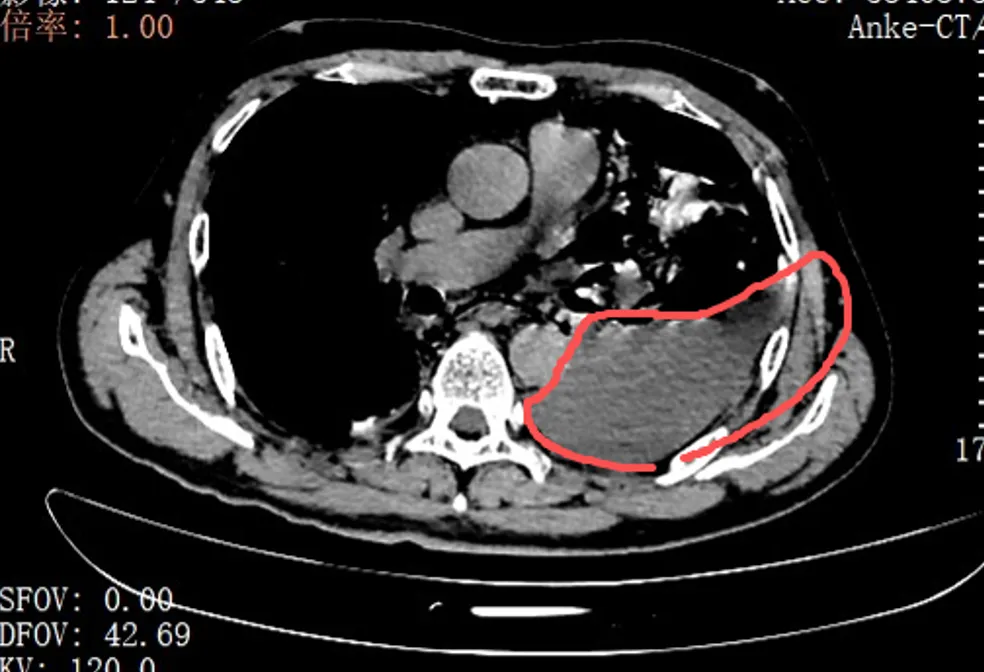

老伴吓得赶紧拨打了120。当晚7点多,他被紧急送到就近医院。胸片结果很快显示:左侧胸腔大量积液。止痛针打了,积液引流做了,但疼痛丝毫没有止住。更糟糕的是,张叔的状态越来越不稳定,眼看就要陷入休克。

凌晨2点,他被紧急转送到北京大学深圳医院。此时,他还不知道,自己的食道,已经在剧烈的呕吐中裂开了一道长达10公分的口子,胃里的食物和胃酸,正源源不断地漏进胸腔里。

很快,口服钡餐的结果印证了他的判断:钡剂从食道下段的裂口处大量漏出,直接进入了左侧胸腔。

自发性食管破裂,也称为Boerhaave综合征,是胸外科最凶险的急症之一,发病急、进展快、死亡率极高。而此时,距离张叔发病还不到24小时——这是救治的黄金窗口期。